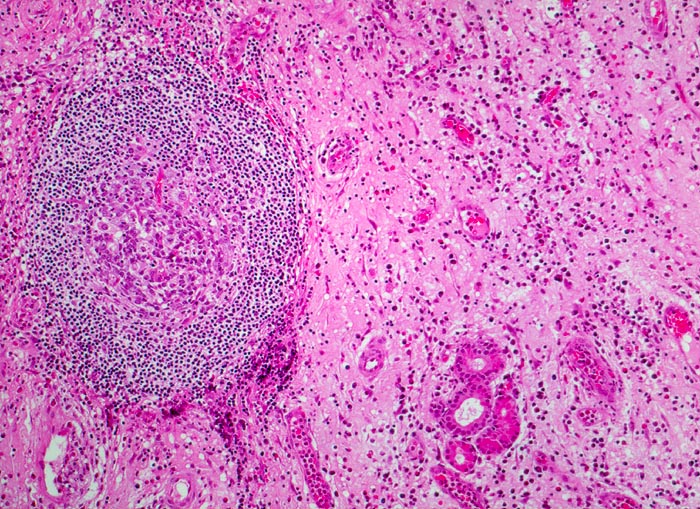

chronische polypöse Rhinitis

Nasenschleimhaut

Vermehrtes ödematöses Stroma mit spindeligen Fibrozyten und gemischtem Entzündungsinfiltrat. Lymphfollikel mit Keimzentrum. Blutgefässe gefüllt mit Erythrozyten und Entzündungszellen. Seromuköse Drüse der Nasenschleimhaut.

Patient mit nicht allergischem Asthma klagt über chronische dumpfe Kopfschmerzen und behinderte Nasenatmung. Bei der anterioren Rhinoskopie sind multiple Polypen der Nasenschleimhaut im Bereich des mittleren Meatus sichtbar.

Histologie

100